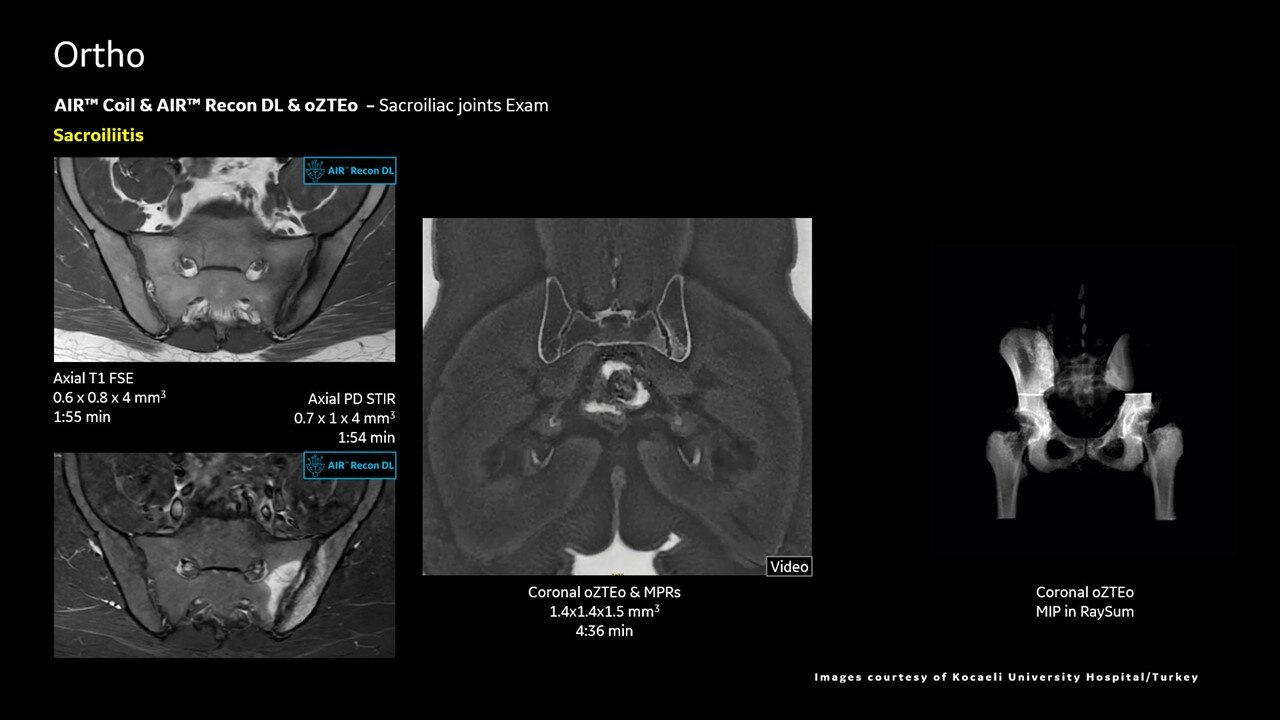

AIR™ Recon DL improves SNR and image sharpness, enabling shorter scan times

Achieve a 25% efficiency gain with Ultra High Efficiency (UHE) gradient system. Fast, clear Total Digital Imaging (TDI) increases SNR by 25%. Improved IQ in 80% of cases without added time. Acquire higher SNR without a time penalty and get images virtually free of artifact with AIR™ Recon DL.***